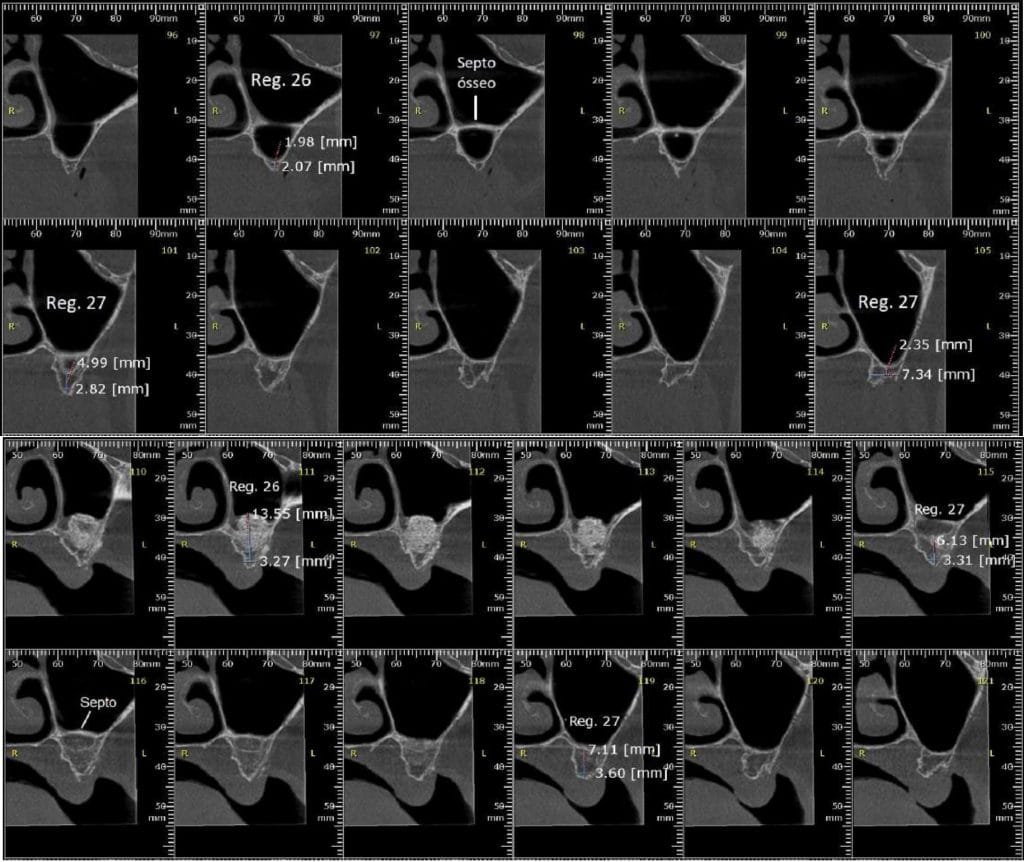

Após 6 meses de maturação óssea e implantes instalados com torque médio de 35 N / cm2.